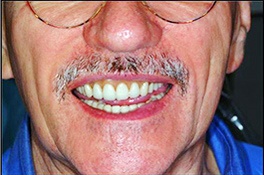

To learn more about the results you can expect from our prosthodontist and team, we encourage you to look through our smile gallery. Call Prosthodontics Atlanta today to schedule an appointment with Dr. Jay S. Smith and learn more about prosthodontics in Atlanta, Georgia, and how it can enhance your smile.

Full Mouth Rehabilitation